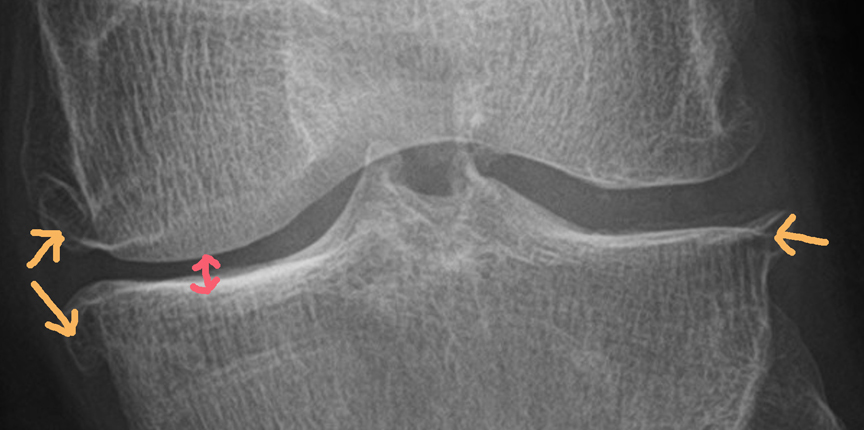

Das obere Röntgenbild zeigt das linke und das untere Bild das rechte Knie.

Die roten Markierungen zeigen den jeweils deutlich verengten Gelenkspalt an den Knieinnenseiten und die orangen Pfeile zeigen die sogenannten Osteophyten.

Osteophyten sind Knochenanbauten, die sich bei fortgeschrittenen Arthrosen bilden.

Was man auf den Röntgenbildern außerdem nicht sehen kann, sind die weiteren Schäden an den Kien wie: Knorpelschäden bis Grad 4, Knochenmarködeme, Meniskusschäden, Bakerzyste, Wasseransammlungen etc., die natürlich auch noch teils heftig vorhanden sind und für mein unrundes und verkorkstes Gangbild sorgen.